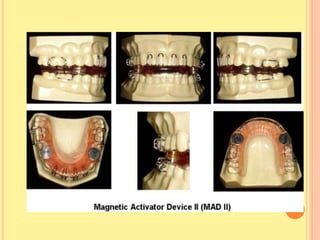

MAGNETIC ACTIVATOR DEVICE (1993)

 Developed by Dellinger, :

 1. MAD I: Correction of lateral mandibular

displacement.

 2. MAD II: Correction of Class II Malocclusion.

 3. MAD III: Correction of Class III Malocclusion.

 4. MAD IV: Correction of Open Bite.